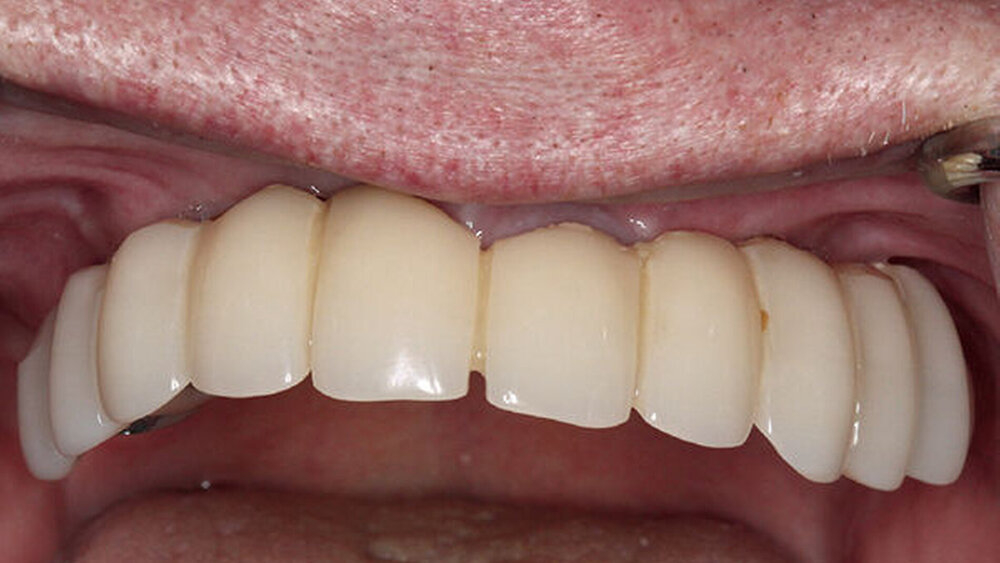

Buhtz: Acht Systeme, um den Wünschen der Überweiser gerecht zu werden. Für alle Systeme bietet die Magellan-Planung eine zuverlässige Lösung mit Blick auf die ideale Positionierung und prothetische Versorgung. Wir mussten seither noch nie „umplanen“. Auch das macht es natürlich für den Patienten kostengünstiger. Inzwischen nutzen wir auch die Mitte 2016 eingeführte „Full-arch-Versorgung“ mit ICX-Imperial, gewissermaßen die Weiterentwicklung des Magellan-Konzepts.

Buhtz: Korrekt, die Voraussetzung ist lediglich die Generierung von DICOM- und STL-Daten, die im Computer exakt übereinandergelegt werden können. Dann erfolgen die Behandlungsplanung wie gewohnt mit ICX-Magellan und die provisorische ‧Versorgung mit dem präfabizierten, chairside hergestellten verklebten PMMA-Provisorium (ICX-‧Smile‧bridge). Seit eineinhalb Jahren arbeiten wir zudem mit dem medentis Fräszentrum Denta5 zusammen.

Die ideal prothetisch ausgerichtete Implantatposition ist der wohl wichtigste Erfolgsfaktor in der Implantologie. Mit ICX-Magellan lässt sich das einfach, schnell und kostengünstig realisieren.